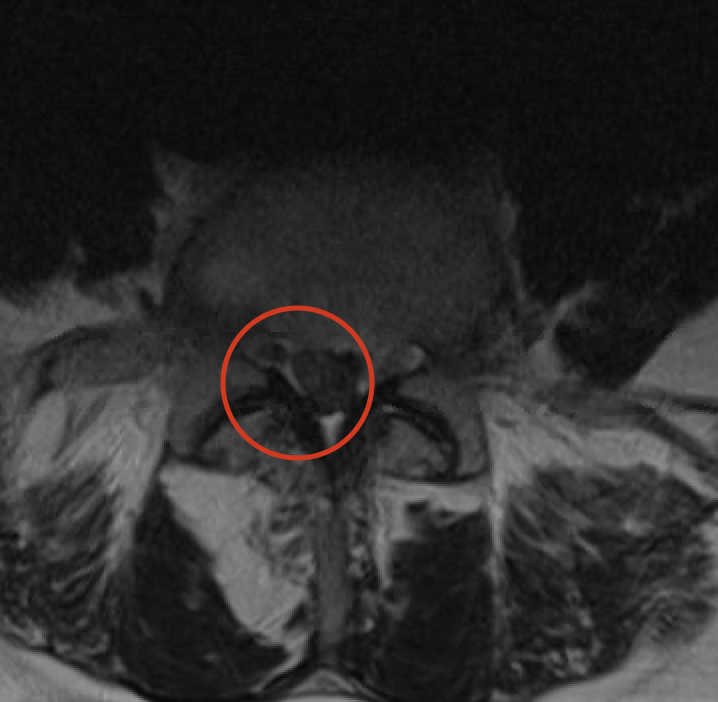

Discus hernia betekent in het Nederlands breuk (= hernia) van de tussenwervelschijf (= discus). Een tussenwervelschijf bestaat immers uit een centraal zacht gedeelte en een omliggende ring. De breuk ontstaat in de buitenste ring waardoor het zachte gedeelte naar achter schuift en druk geeft op het ruggenmerg of zenuwen. Hierdoor kan pijn in het been ontstaan (in de volksmond omschreven als ischias, sciatique of ingeklemde zenuw) wat het typische symptoom is van een hernia in de lage rug. Een hernia kan ook aanwezig zijn zonder symptomen en moet dan ook niet verder behandeld worden.

Het ideale onderzoek is een NMR (=MRI). Het levert ons de beste beelden en gebruikt geen nadelige X-stralen. Soms wordt ook een CT scan van de lumbale wervelzuil gevraagd.